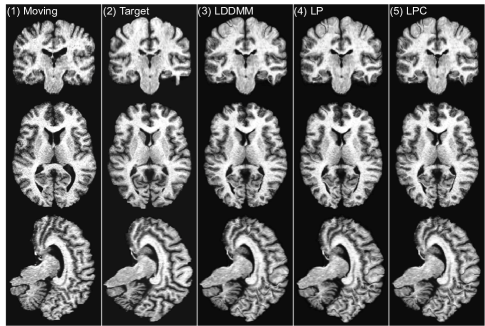

In this experiment, we use a sliding window stride of 14 for both the prediction network and the correction network during evaluation. We mainly compare the following three LDDMM-based -methods: (i) the numerical LDDMM optimization approach (LO) as implemented in PyCA, which acts as an upper bound on the performance of our prediction methods; and two flavors of Quicksilver: (ii) only the prediction network (LP) and (iii) the prediction+correction network (LPC). Example registration cases are shown in Fig. 9.

LPC 0.415±0.287plus-or-minus0.4150.287\pagecolor{green!30}0.415\pm 0.287 0.469±0.327plus-or-minus0.4690.3270.469\pm 0.327 0.509±0.359plus-or-minus0.5090.3590.509\pm 0.359 0.546±0.390plus-or-minus0.5460.3900.546\pm 0.390 0.584±0.424plus-or-minus0.5840.4240.584\pm 0.424 0.626±0.464plus-or-minus0.6260.4640.626\pm 0.464 0.676±0.514plus-or-minus0.6760.5140.676\pm 0.514 0.742±0.583plus-or-minus0.7420.5830.742\pm 0.583